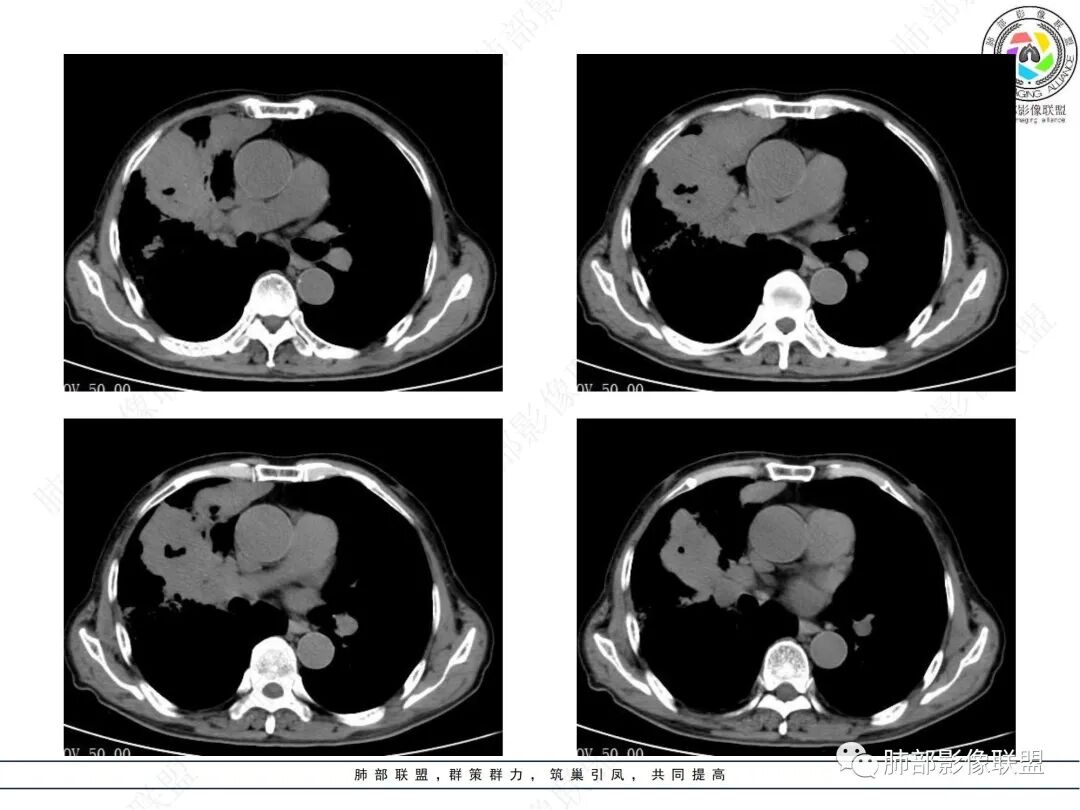

晨读病例,老年男性,乏力,纳差,近来发热,右肺上叶团片状阴影,内见空洞,空洞内壁不光滑,见短液平,增强病灶壁可见不均匀强化,似有边界不清晰的坏死,病灶周围可见片状模糊阴影,考虑恶性病变,鳞癌或腺癌伴感染。

老年男性,肺气肿背景,右肺较大分叶状肿块,密度不均,内坏死空洞形成,坏死区边界不规则,周围多发斑片蜂窝状、网格状高密度影,考虑鳞癌合并感染

右肺上叶及中叶不规则肿块伴周围模糊影,其内小叶间质结节样改变,肿块不均匀强化,坏死及空洞,坏死边界不清,血管显示尚可,考虑腺癌,鉴别淋巴瘤

老年男性,有咳嗽发热。右肺中上叶团状软组织肿块,周围磨玻璃渗出改变,病灶内密度不均,可见低密度坏死及空洞影,空洞内壁凹凸不平,近肺门侧可见明显大面积坏死。近端支气管堵塞不明显。考虑恶性肿瘤伴感染,腺癌?鉴别鳞癌,感染性病变。

右肺上叶团片状阴影,内见空洞,空洞内壁不光滑,偏心,,增强不均匀强化,内有边界不清晰的坏死,病灶周围可见片状模糊阴影,右下肺也有磨玻璃病灶,Crp高,腺癌

70岁男性,发烧病史,右肺巨大肿块,边缘分叶,内部空洞,洞内见附壁结节,局部支气管阻塞,肿块周围见大片阻塞性炎症;实验室检查,炎性指标增高;考虑恶性肿瘤伴阻塞性肺炎,鳞癌可能。

老年男性,乏力,纳差,发热。右肺上叶团片状阴影,密度不均,可见低密度坏死,坏死边界不清,可见空洞形成,见短液平;增强病灶呈不均匀强化,其内血管边缘模糊毛糙;病灶周围可见斑片状渗出病灶,支气管未见明确阻塞。综上考虑肺癌伴感染,鳞癌可能。

老年男性,纳差和发热,炎症指标明显。右肺磨玻璃影伴有肿块,肿块呈膨胀性生长,内部没有气管影。首先考虑感染,并有肿瘤的表现。考虑鳞癌合并感染

右肺上叶实变,密度不均,内可见小气液平,周磨玻璃影,斜裂稍内凹,右下肺可见斑片影,强化可见血管走行自如,右侧胸腔少量积液,考虑感染性病变,努卡?放线菌?

老年男性,肺气肿背景,右肺上叶及中叶大范围实变影,边界不清,支气管通畅,其内见边缘膨隆软组织块影伴不规则坏死、空洞,增强扫描不均匀强化,洞壁显示不清,血管稍变细,实变影内另见多发囊样影,右肺下叶小片状影,病灶跨叶,炎性指标增高,感染应该有的,不除外合并恶性肿瘤(鳞癌?腺癌?)

男,70,反复乏力、纳差20天,发热1天。胸部CT:肺气肿背景,右肺上叶中叶大团片影,实变十磨玻璃渗出。增强实性斑片影内密度不均,可见多发低密度坏死及不规则空洞影,空洞内壁尚光滑,血管边缘模糊。支气管管壁增厚,管腔通畅。右下叶可见小片渗出影。考虑支气管肺炎进展?病原考虑能形成肉芽肿、坏死空洞的微生物,TB?奴卡?鉴别鳞癌。

老年男性,乏力纳差,进食量明显下降,发热,后期少许黄脓痰,无咯血。无胸痛。未提口腔卫生情况,发热时间段不明确,肺气肿背景,气管内痰拴还是其他?觉得是外朝内进展病灶,右肺多叶段病灶,支气管通畅,支气管壁弥漫增厚,实变病灶内有坏死,坏死边界比较清晰,血管破坏不明显,周围散在磨玻璃,边界模糊,无树芽,实变内可疑小钙化,右侧胸水,肺门纵隔淋巴结无明显肿大。病史不太支持化脓菌感染,真菌里隐球强化不太支持,结核需要排除,厌氧菌感染带排,冠状位矢状位病灶觉得类圆形,临床肿瘤也是不能轻易排除的